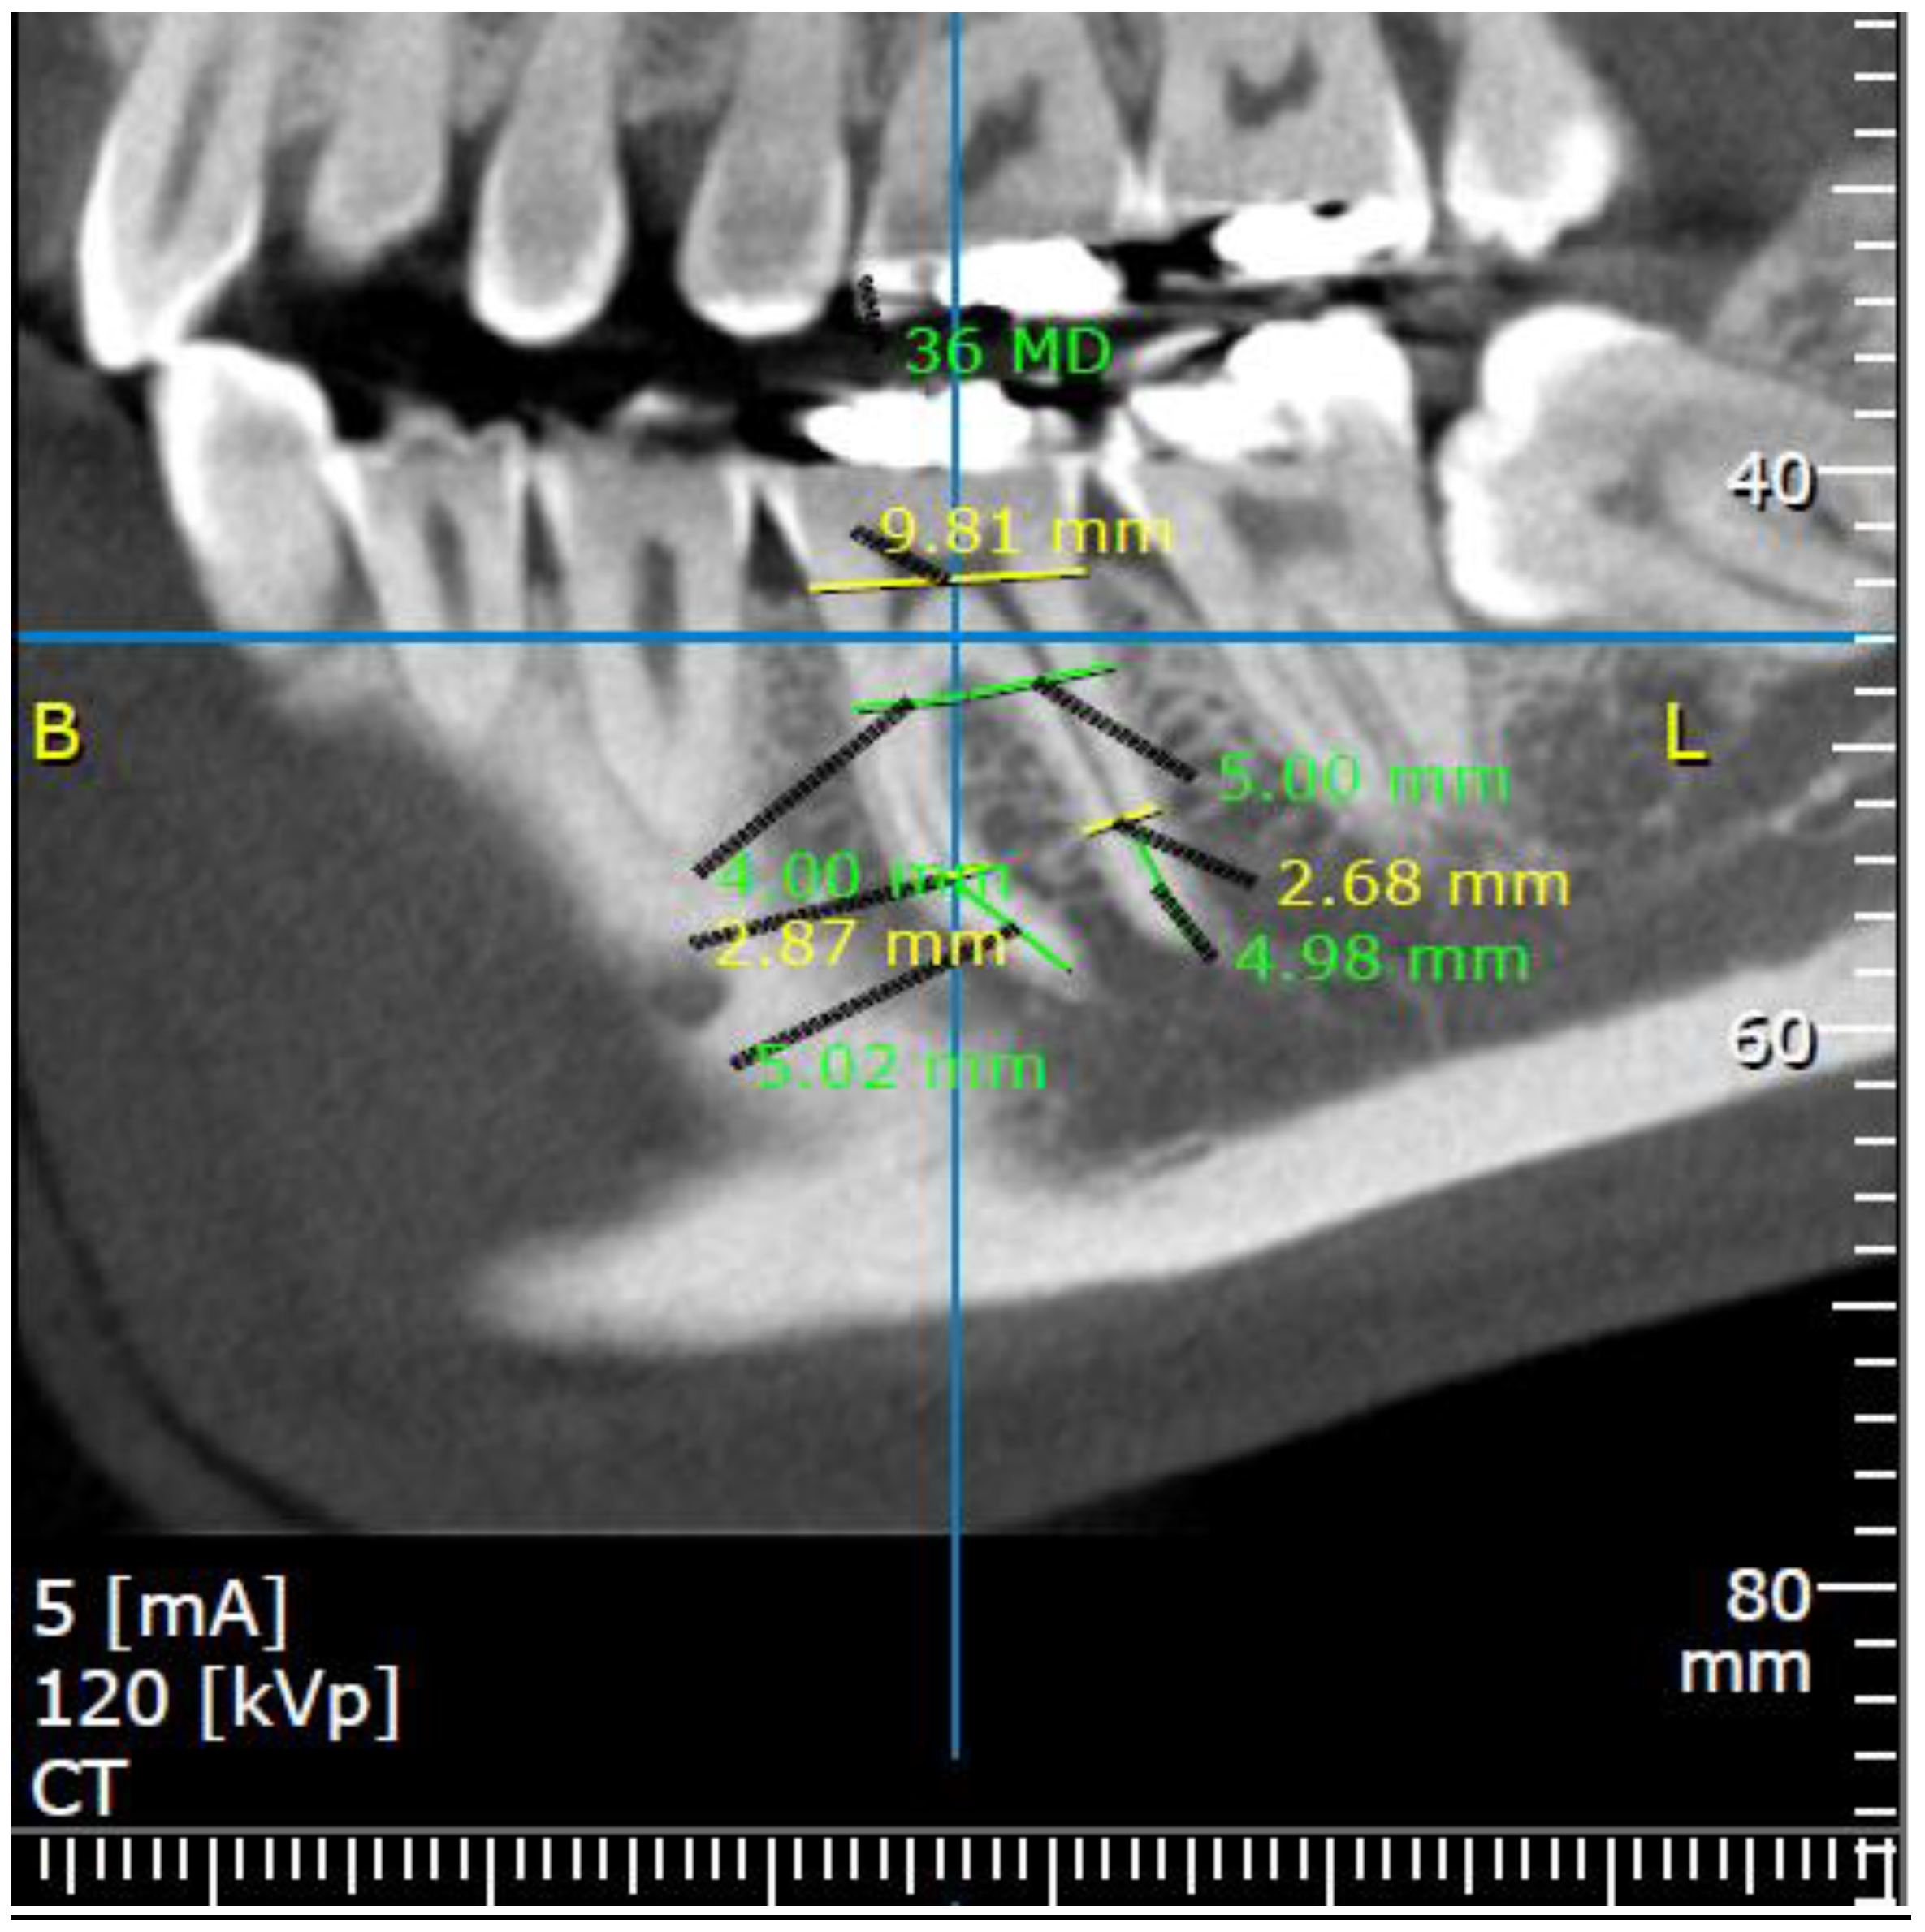

2.3. Measurements

3.2.1. Mesiodistal Aspect